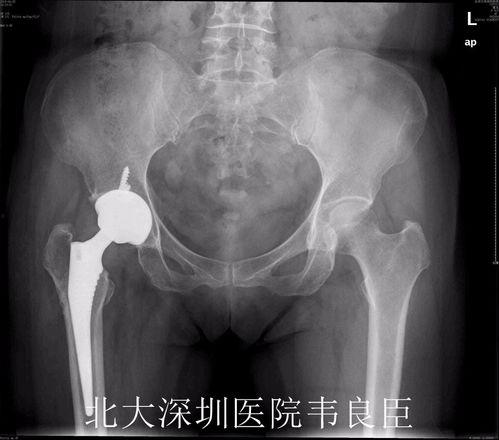

首先,医生会在患者的髋关节处切开一个小口,然后取出坏死的股骨头。接着,医生会植入一个新的股骨头,这个股骨头通常由金属制成,具有良好的生物相容性。

视频中,我们可以看到医生正在小心翼翼地取出坏死的股骨头,并植入新的股骨头。手术过程中,医生需要确保新股骨头与髋臼紧密贴合,以恢复髋关节的正常功能。